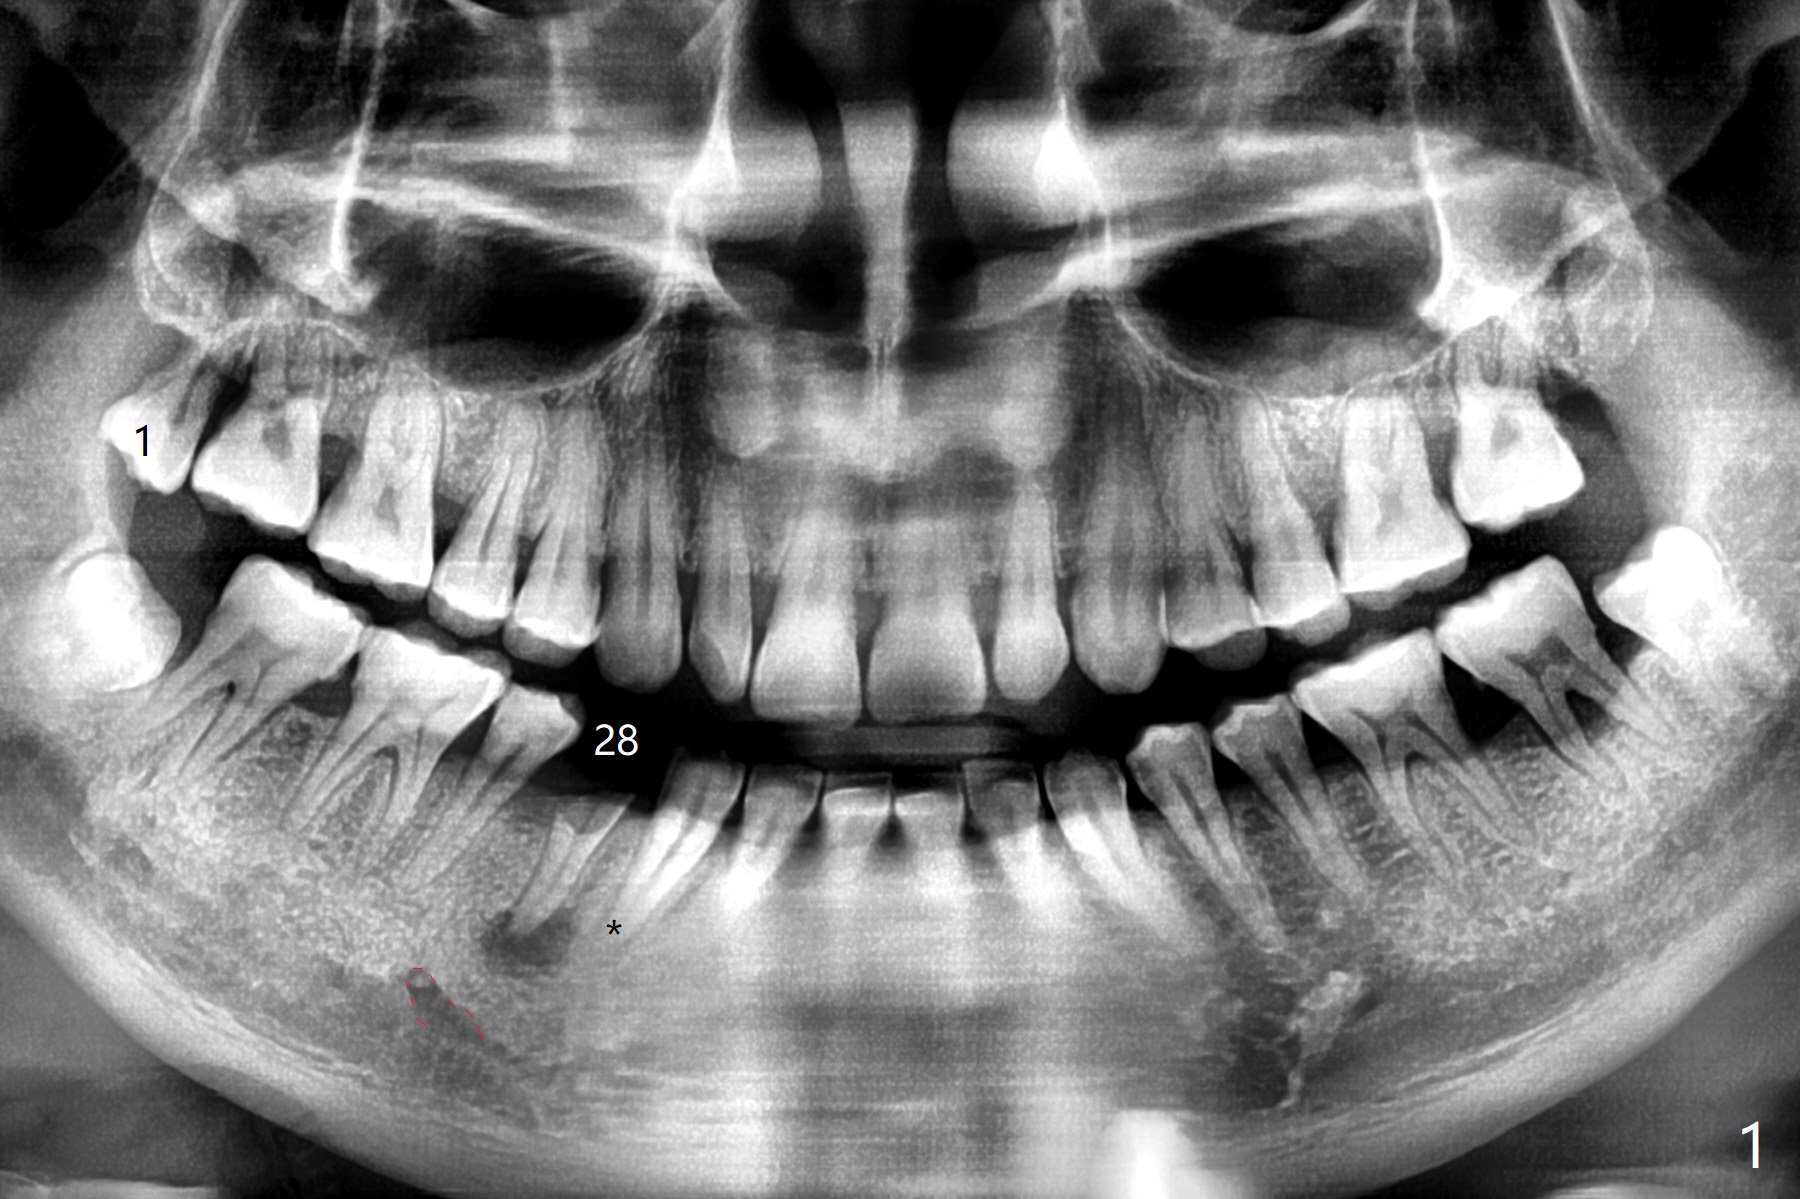

A 40-year-old man (hypertension) without history of cleaning presents to clinic with residual root at #28 (Fig.1). Next visit, SRP will be performed on the right side with extraction of the tooth #1; PA to be taken for #28. Following SRP on the left side at next appointment, extraction and implant (IS) will be done for the tooth #28. Because of the Mental Loop (buccal, red dashed line) and the distally curved apex of the tooth #27 (*), the initial osteotomy will be established distolingual aspect of the socket for ~ 4 mm past the bottom of the socket. Take PA immediately and change the trajectory if needed.